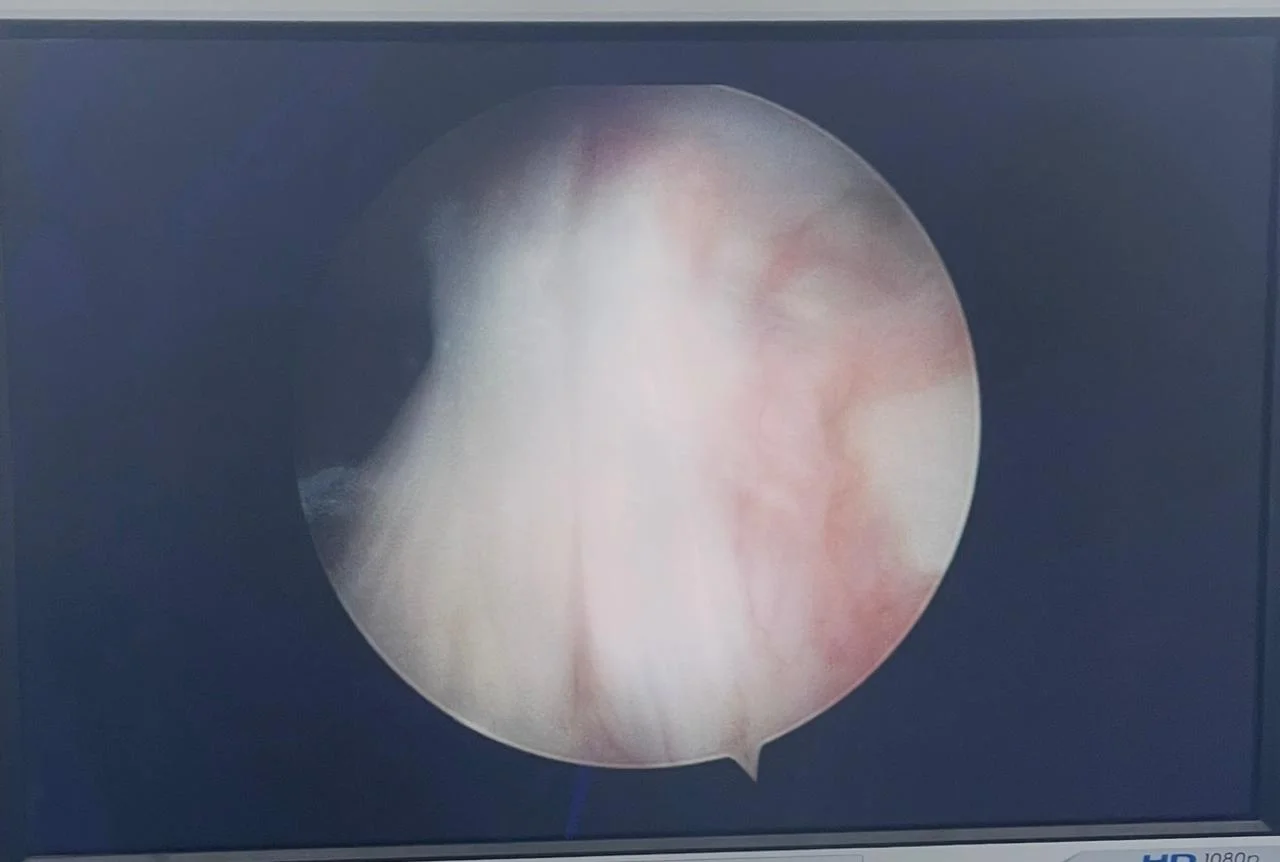

Lesión Resonancia magnética mostrando ruptura de ligamento cruzado anterior (LCA) en rodilla

Recuperación Recuperación tras cirugía artroscópica de reconstrucción de LCA y menisco - Medicina deportiva

Medicina Deportiva

Reconstrucción de

Ligamento Cruzado (LCA)

• Perfil del Paciente: Masculino, 24 años. Deportista recreativo (fútbol).

• Diagnóstico: Ruptura completa de ligamento cruzado anterior con lesión de menisco medial.

• Procedimiento: Artroscopia de rodilla: Reconstrucción de LCA con autoinjerto y reparación meniscal.

• Evolución: Retorno progresivo al entrenamiento a los 6 meses. Recuperación total de la estabilidad articular.